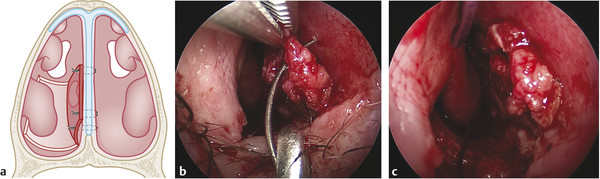

Avoid mucosal tearing during harvesting of the flap. Verify that the flap is pedunculated at the caudal part of the septal mucosa to guarantee the blood supply (Fig. 17‑3).

Rotation and elevation of the flap. Verify the full coverage of the perforation with safety margins (at least 3 mm) to avoid septal reperforation in case of retraction of the flap. (Fig. 17‑3, Fig. 17‑4).